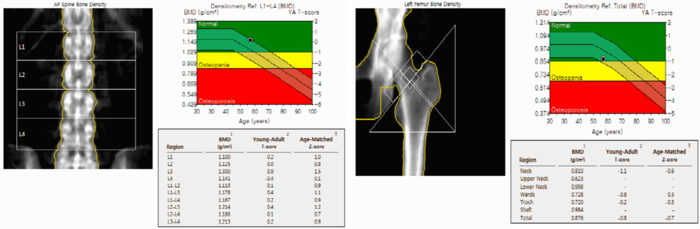

골밀도 검사 결과는 일반적으로 T-score라는 지표를 통해 판단합니다. T-score는 건강한 젊은 성인의 평균 골밀도와 비교하여 현재 골밀도 상태를 평가하는 지표입니다.

T-score 기준은 다음과 같습니다.

- -1.0 이상 : 정상

- -1.0 ~ -2.5 : 골감소증

- -2.5 이하 : 골다공증

- 척추와 고관절 골밀도를 정확하게 측정